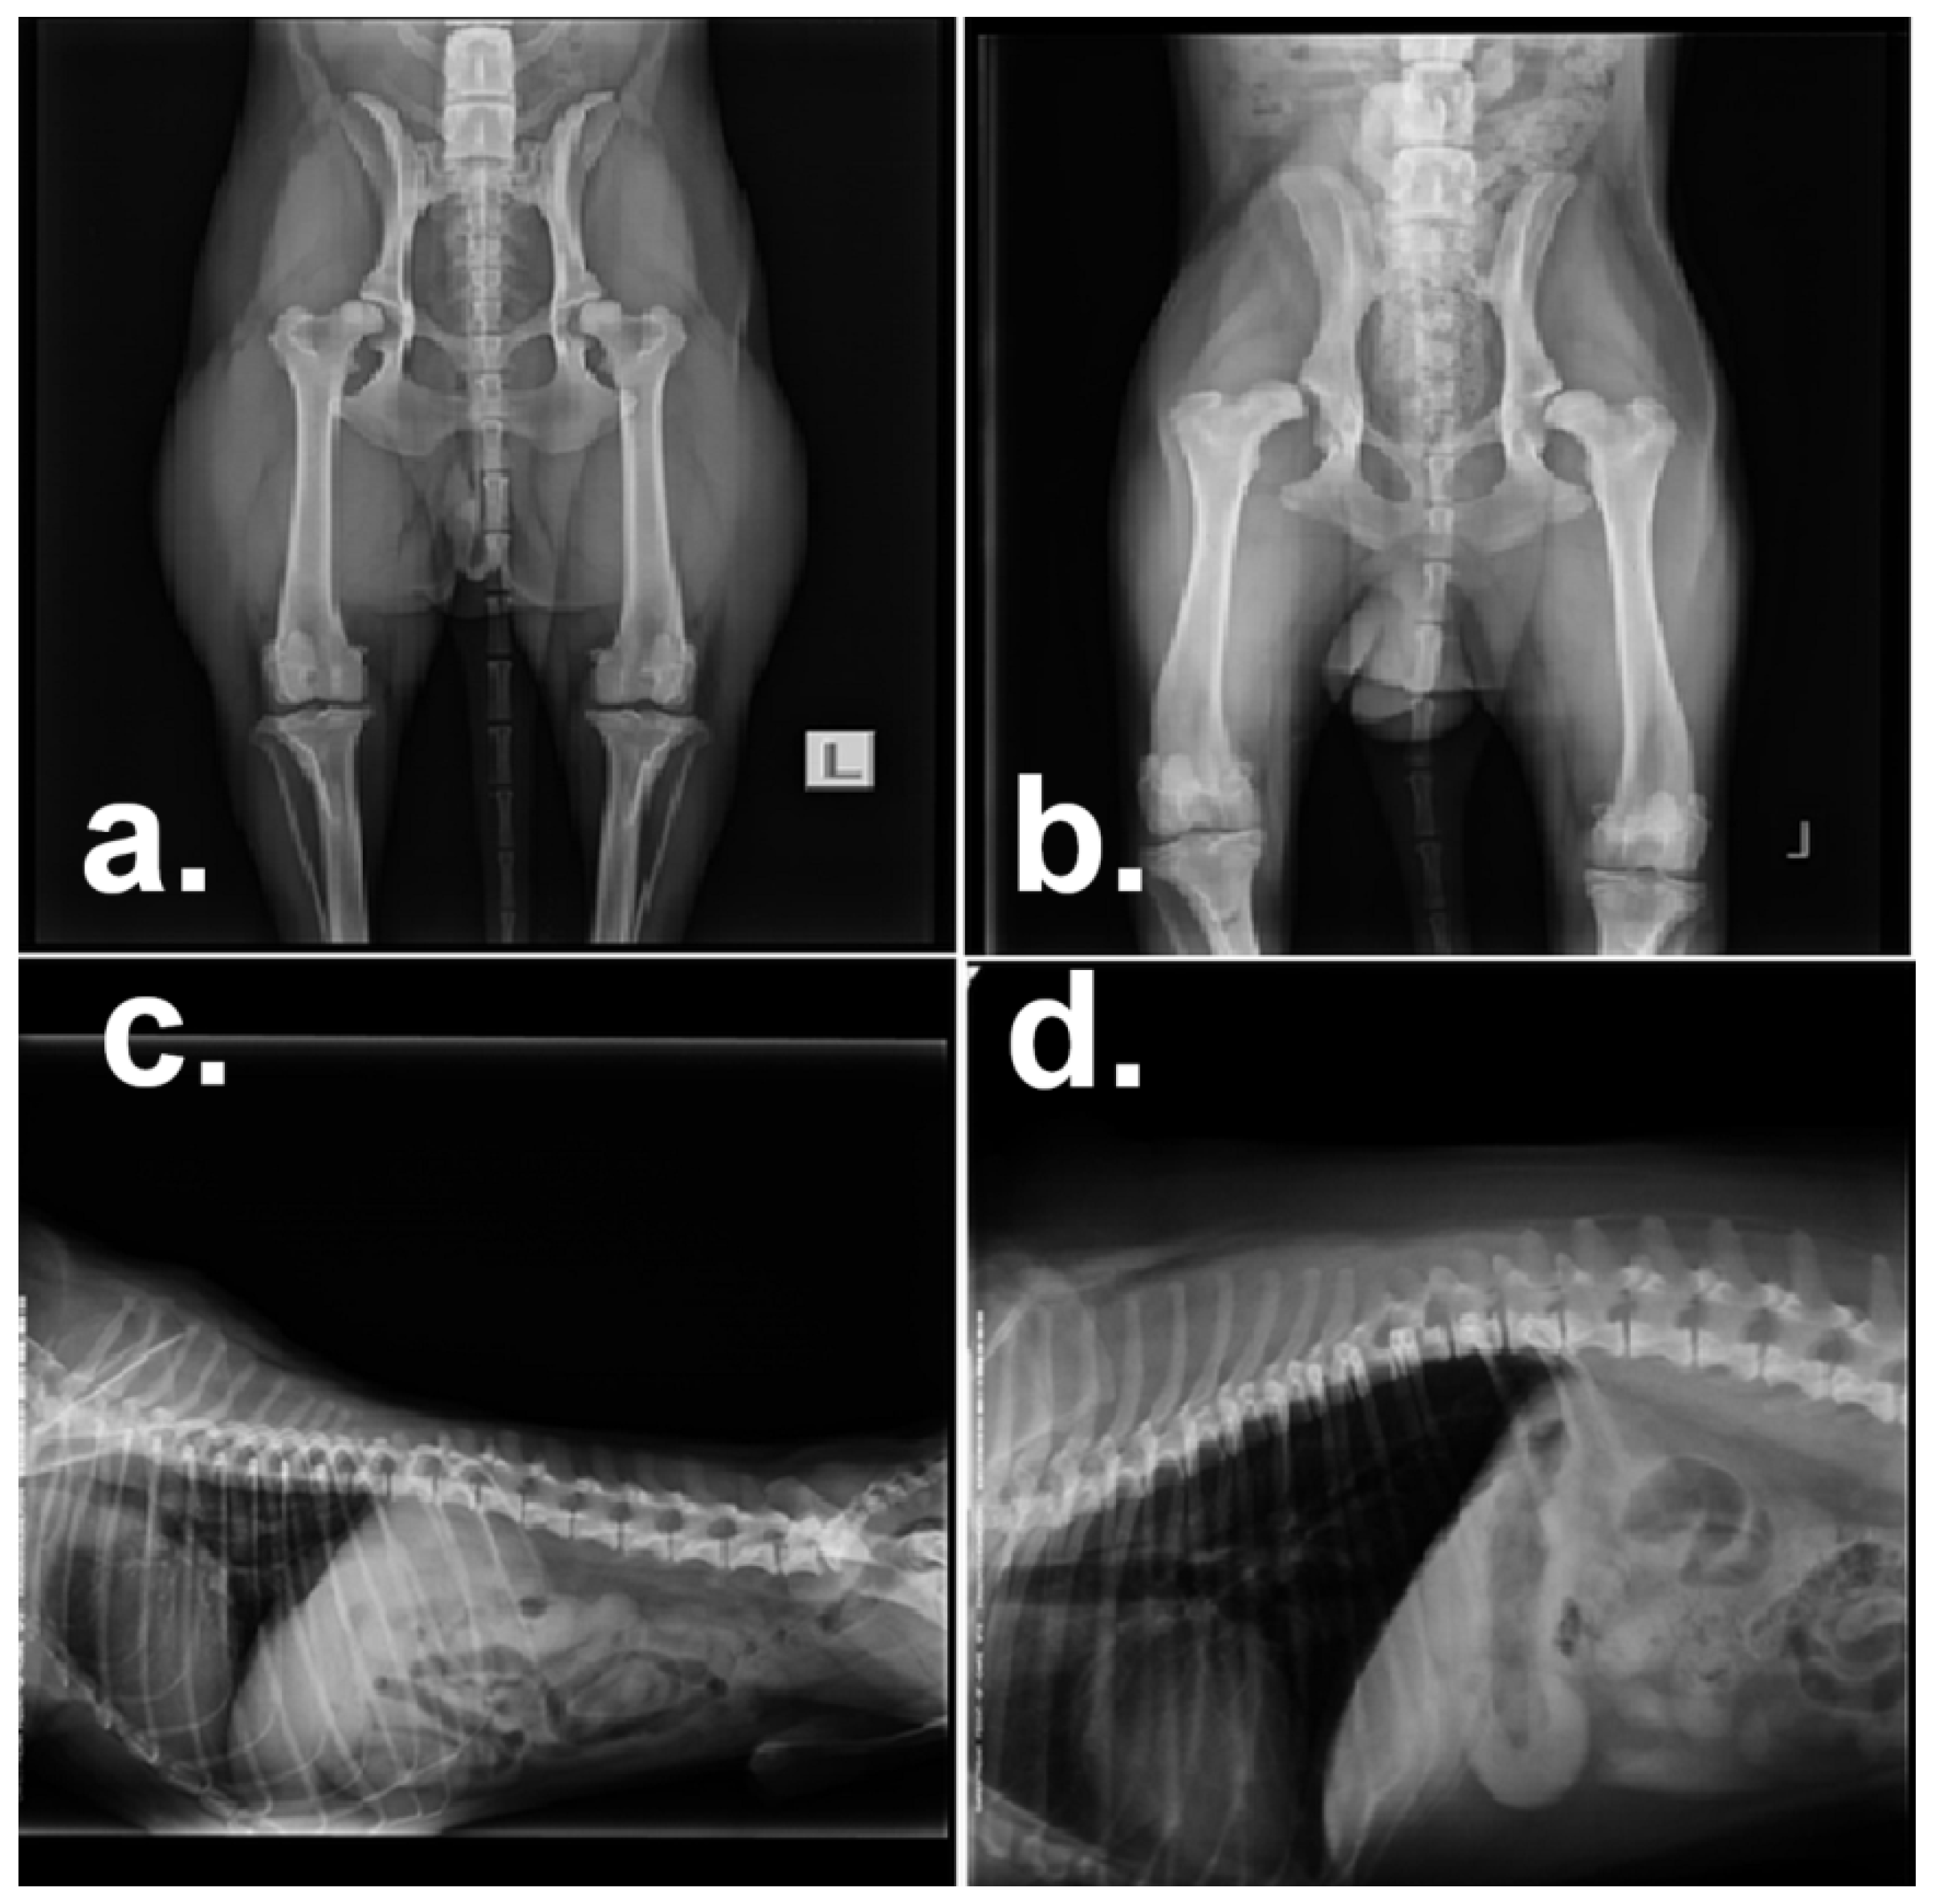

| 9 | Saint Bernard, female | Moderate pain in the right hip, intermittent lameness during the increased effort, extension of the right hind leg not utterly possible in comparison with the left leg. Presumptive diagnosis: Hip dysplasia. Recommendation: Radiographic examination under anesthesia | pROM exercises, Drug treatment Previcox, 227 mg 1½ × 1/day, ten days |